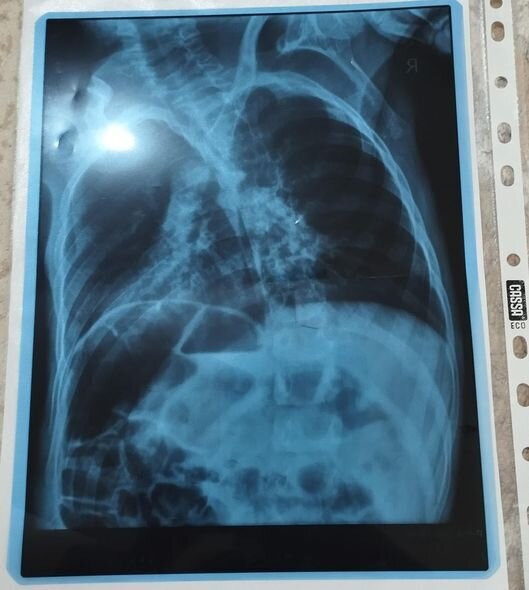

O qeyd edib ki, övladı serebral iflicdən əziyyət çəkir.

Nərminə Əzizova bildirib ki, Ömərə hazırda sətəlcəm diaqnozu qoyulub:

"Öməri soyuq havalarda qətiyyən çölə çıxarmırıq. Qış ərzində ancaq evdə olur. Evin istisinə o qədər öyrəşir ki, çox az müddətə çölə çıxanda xəstələnir. Həkimlər ona sətəlcəm diaqnozu qoyublar. Mənim Ömərlə birgə üç övladım var, Ömərin xəstəliyi bizi əldən salıb - heç nəyi çatdıra bilmirik. Ömərin müalicəsi üçün hazırda 600 manata ehtiyacımız var. Yardımsevər şəxslərdən bizə dəstək olmaqlarını xahiş edirəm".